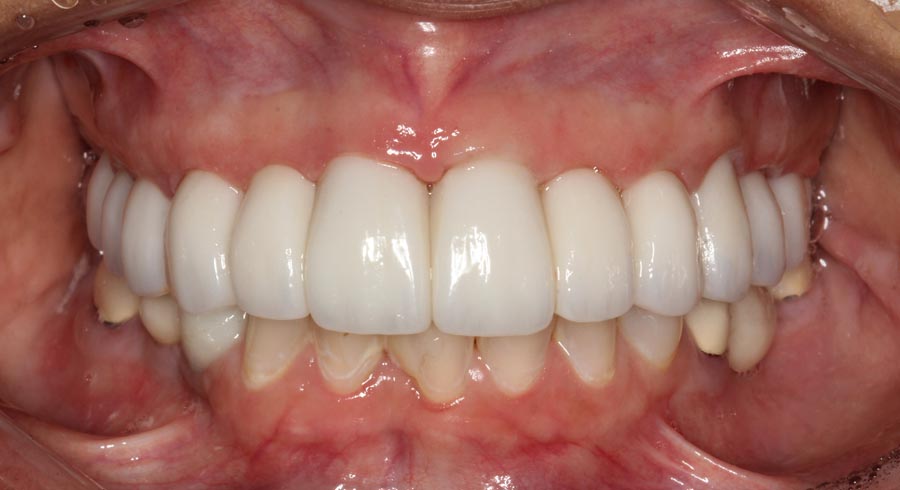

Smile GalleryImplant RestorationsFull Mouth Implant Restoration Full arch zirconia implant bridge (full smile) 1 of 37 Pre-op full smile Pre-op lips retracted Pre-op panoramic x-ray Extraction of strategic teeth Placement of implants Extraction of some remaining teeth after verification of adequate implant stability Occlusal view Post-op panoramic x-ray Immediately fabricated provisional restoration (tissue side view) Immediately fabricated provisional restoration (occlusal side view) Immediate provisional delivered on day of surgery Immediate provisional 2 weeks later Scalloped tissue developed from the provisional at 2 weeks Jig used for making a master impression Provisional in place (full smile) Provisional in place (lips retracted) Provisional in place (right side) Provisional in place (left side) Wax try-in (full smile) Wax try-in (right side full smile) Wax try-in (left side full smile) Wax try-in (full face, lips together) Wax try-in (full smile) Wax try-in (right side) Wax try-in (left side) Wax try-in (lips retracted) Full arch zirconia implant bridge on master cast (frontal view) Full arch zirconia implant bridge on master cast (occlusal view) Implant positions and soft tissue representation on master cast (occlusal view) Soft tissue representation on master cast (frontal view) Full arch zirconia implant bridge (tissue side view) Soft tissues on day of delivery (occlusal view) Soft tissues on day of delivery (frontal view) Full arch zirconia implant bridge delivered (lips retracted) Full arch zirconia implant bridge (lips retracted, close up) Post treatment panoramic x-ray Full arch zirconia implant bridge (full smile)